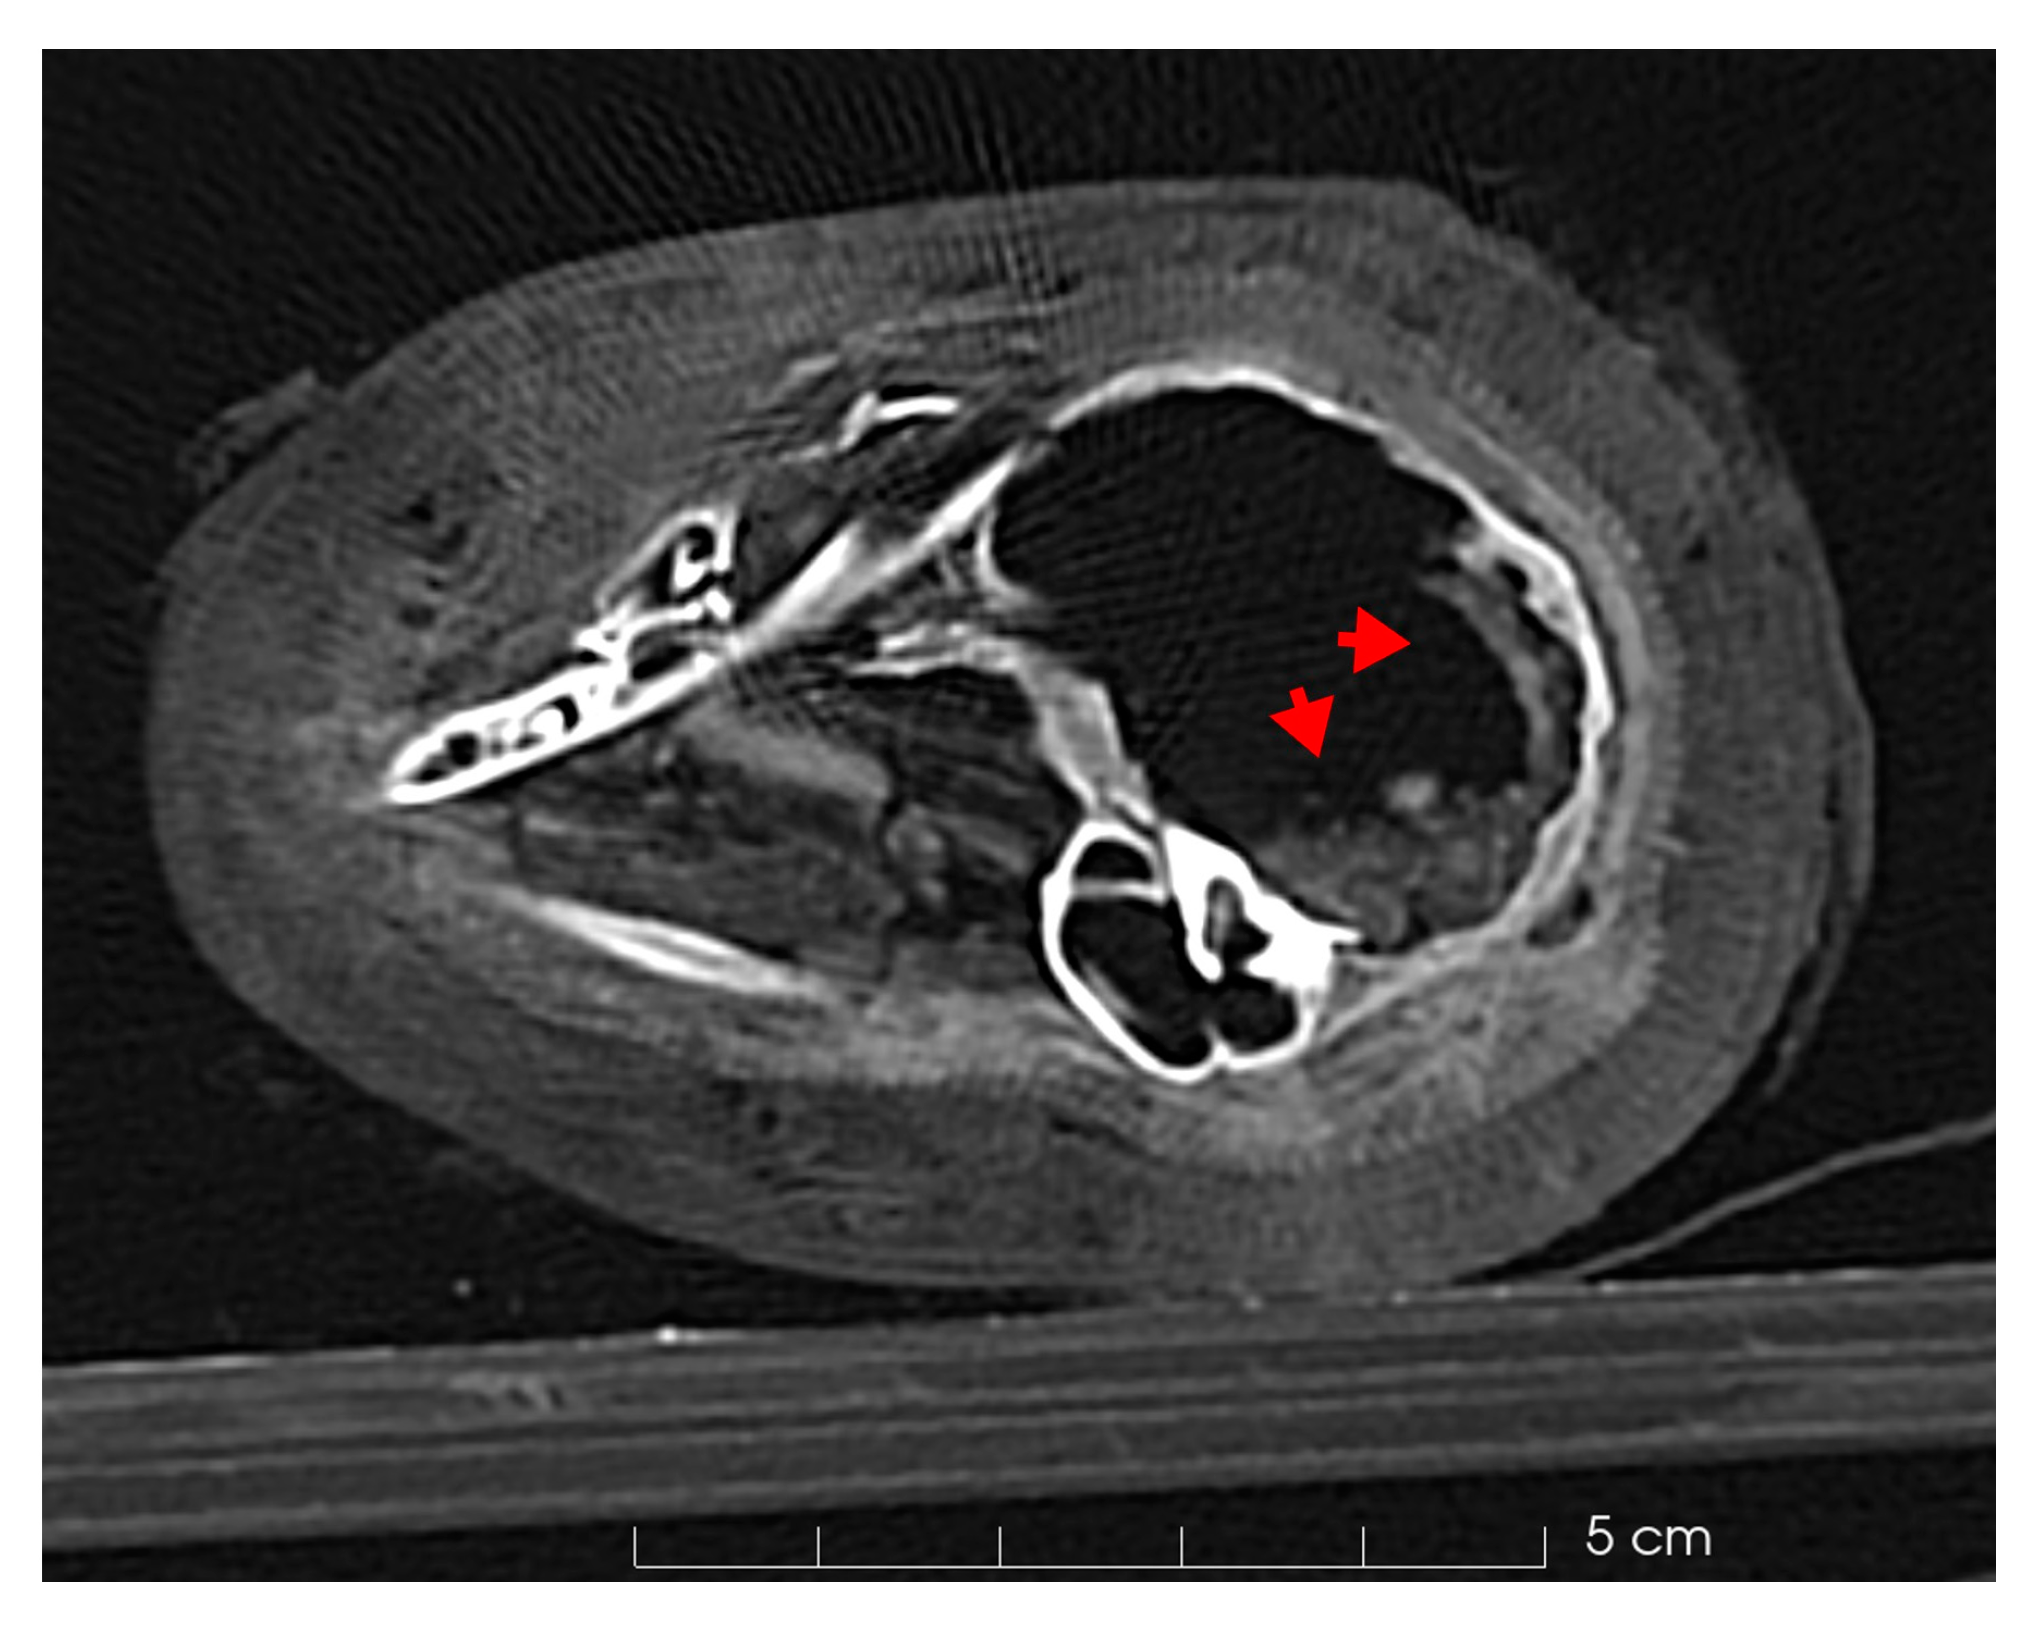

Deeper analyses revealed several bone fractures. The cranial region showed a significant fracture. The sides of the foramen magnum and the first cervical vertebra appeared discontinuous and damaged; additionally, the atlas had a clear fracture in the ventral side, where the arch of the vertebra is separated from the rest of it (Figure 5a,b).

Figure 5.

The head of the cat mummy. (a) Axial CT of the foramen magnum depicts a discontinuity of the occipital bone compatible with the fracture of the atlas (b), where the ventral arch is separated from the rest of the body (red arrow, axial CT scan). (c) Axial CT scan of the foramen in the occipital bone (2 mm). (d) 3D rendering of the skull with the foramen.

Furthermore, the occipital bone of the cat’s skull featured a centrally located posterior rounded foramen measuring 2 mm in diameter (Figure 5c).

Previous research on mummified cats has shown that a common method to sacrifice young cats was to break their necks by twisting them or hitting them on their head [46,48,51]. These procedures left prominent marks near the cervical vertebrae and occipital portion of the skull [48]. Based on a comparison between our cat mummy and cases reported in the literature [19,46,48], it is feasible to conclude that the death may be attributed to a neck dislocation with visible fractures, as shown in Figure 5a,b.

Additionally, the CT scans highlighted the presence of a perfectly rounded and symmetric foramen in the occipital bone (Figure 5c,d). Various hypotheses have been proposed regarding its origin, suggesting it may be related to a traumatic injury, such as a small perforation by a small tool, given its 2 mm dimension, or it could represent an anatomical feature of the skull that occasionally forms. However, the exact nature of this foramen cannot be definitively ascertained from the CT scan alone, as it requires more detailed analysis for a thorough understanding.